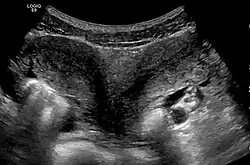

| Ultrasound showing didelphys | |